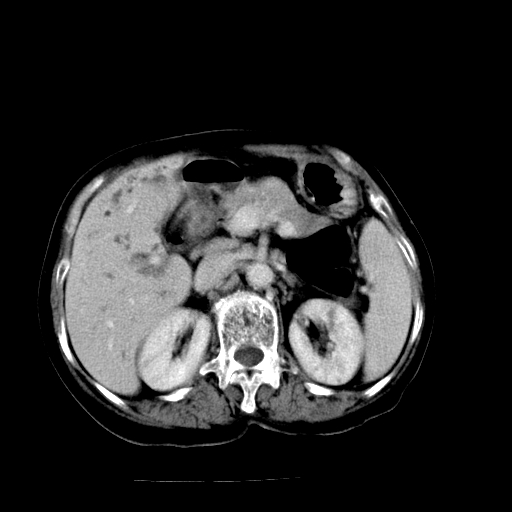

以下是引用随光逐影在2009-4-7 8:21:00的发言:[br]肝内外胆管多发性结石并肝内外胆管扩张;胆系感染。